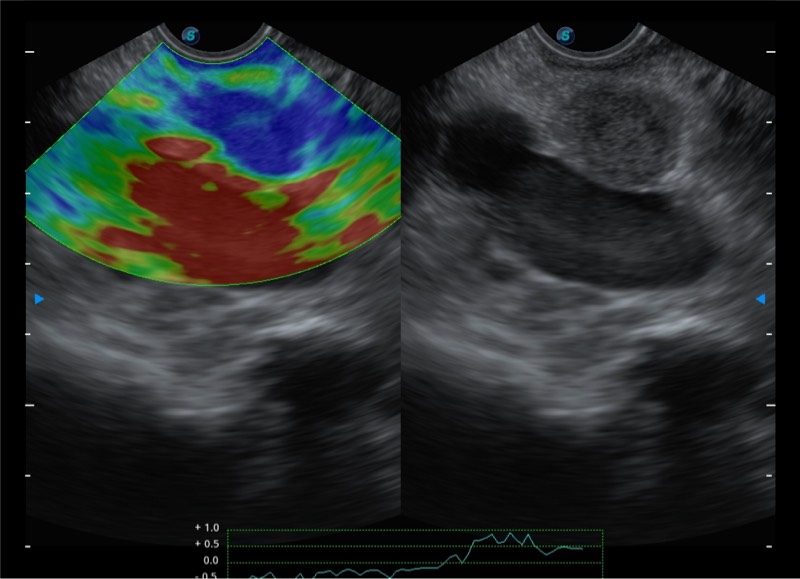

搭载百万级CMOS成像技术

及自主研发凸阵换能器,

可呈现优质的内镜和超声画面

基于二十年的超声技术积累,球速体育入口提供了最新一代的独立超声主机,在提供高质量图像的同时满足多学科使用。具备常见多普勒技术并提供弹性成像、声学造影等高端影像技术。新一代传感器具有更强的抗干扰能力并减少图像伪影。

150°超声扫描角度

4-12MHZ宽频输出